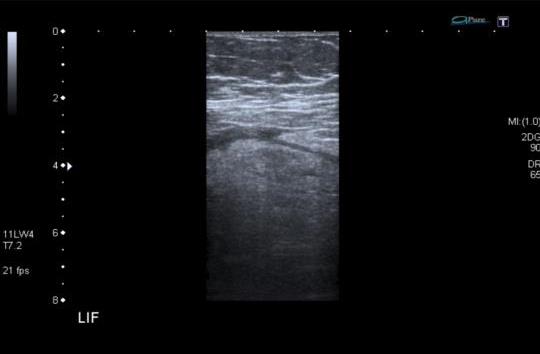

Representative sonographic images of the abdominal scan are shown below:

![]() |

|

Figure 4. Targeted longitudinal sections over the LIF |